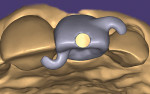

Prior to surgery and upon completion of the virtual implant planning session, the anti-rotation wings are virtually added to the provisional crown. They are constructed to create a counterclockwise-resistant torque by resting on the teeth adjacent to the planned implant location. To aid in communication with the laboratory, the wings should be fabricated to resemble the hurricane symbol when viewed from the incisal edge (Figure 6). These wings should not extend from the facial embrasures of the provisional, nor should they make complete intimate contact with the adjacent teeth, but only rest upon them. While having complete contact with adjacent teeth would make the wings stronger, it creates challenges for easy esthetic wing removal chairside after torquing the abutment screw. Thus, the wings ideally should resemble arches, with a single-point contact originating near the line angles of the provisional and inserting near the line angles of adjacent teeth (Figure 7).